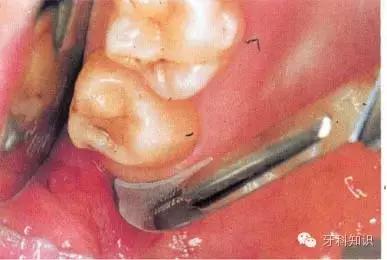

用缝线穿过舌侧软组织并将其拉向舌侧,以避免其受损并保证术区视野清晰。切割牙冠前先将牙根挺松。图示为用合适的牙挺楔入挺松的牙根下面

尽管事先已挺松牙根,但仍无法顺利掏出。于是用纺锤形车针扩大牙槽窝,操作时应紧贴牙槽窝内壁。拔出牙根后可见根尖肥大。这通常与牙骨质增生有关,故不能通过

牙挺施以*力暴**而拔除。术者应尽量避免折裂牙槽窝骨壁